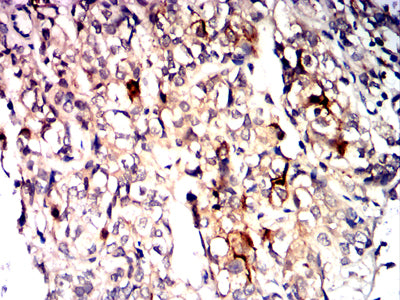

Immunohistochemical analysis of paraffin-embedded human bladder cancer tissues using CD10 mouse mAb with DAB staining.